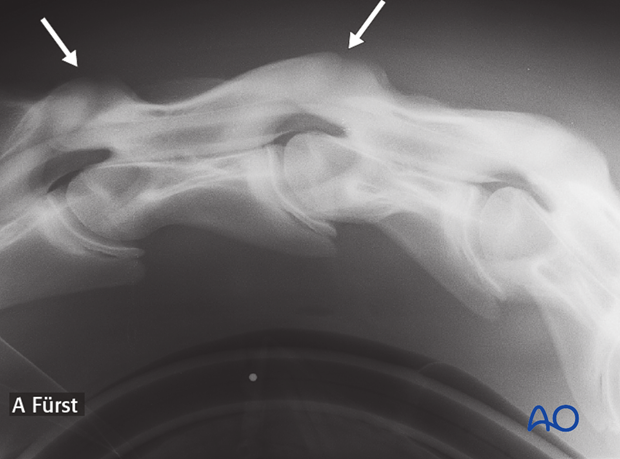

1.5-year-old Warmblood foal with instability of C3-C4-C5.

Preoperative myelography showing the instability of C3-C4-C5 (arrows).